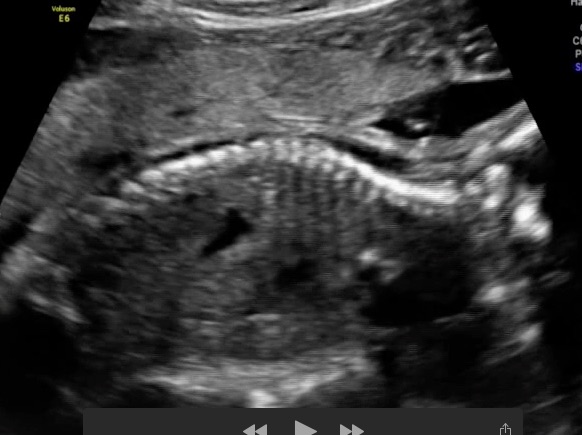

20 week scan pic...boy or girl !!!

Attachment 22644

You need a potty shot at this gestation.